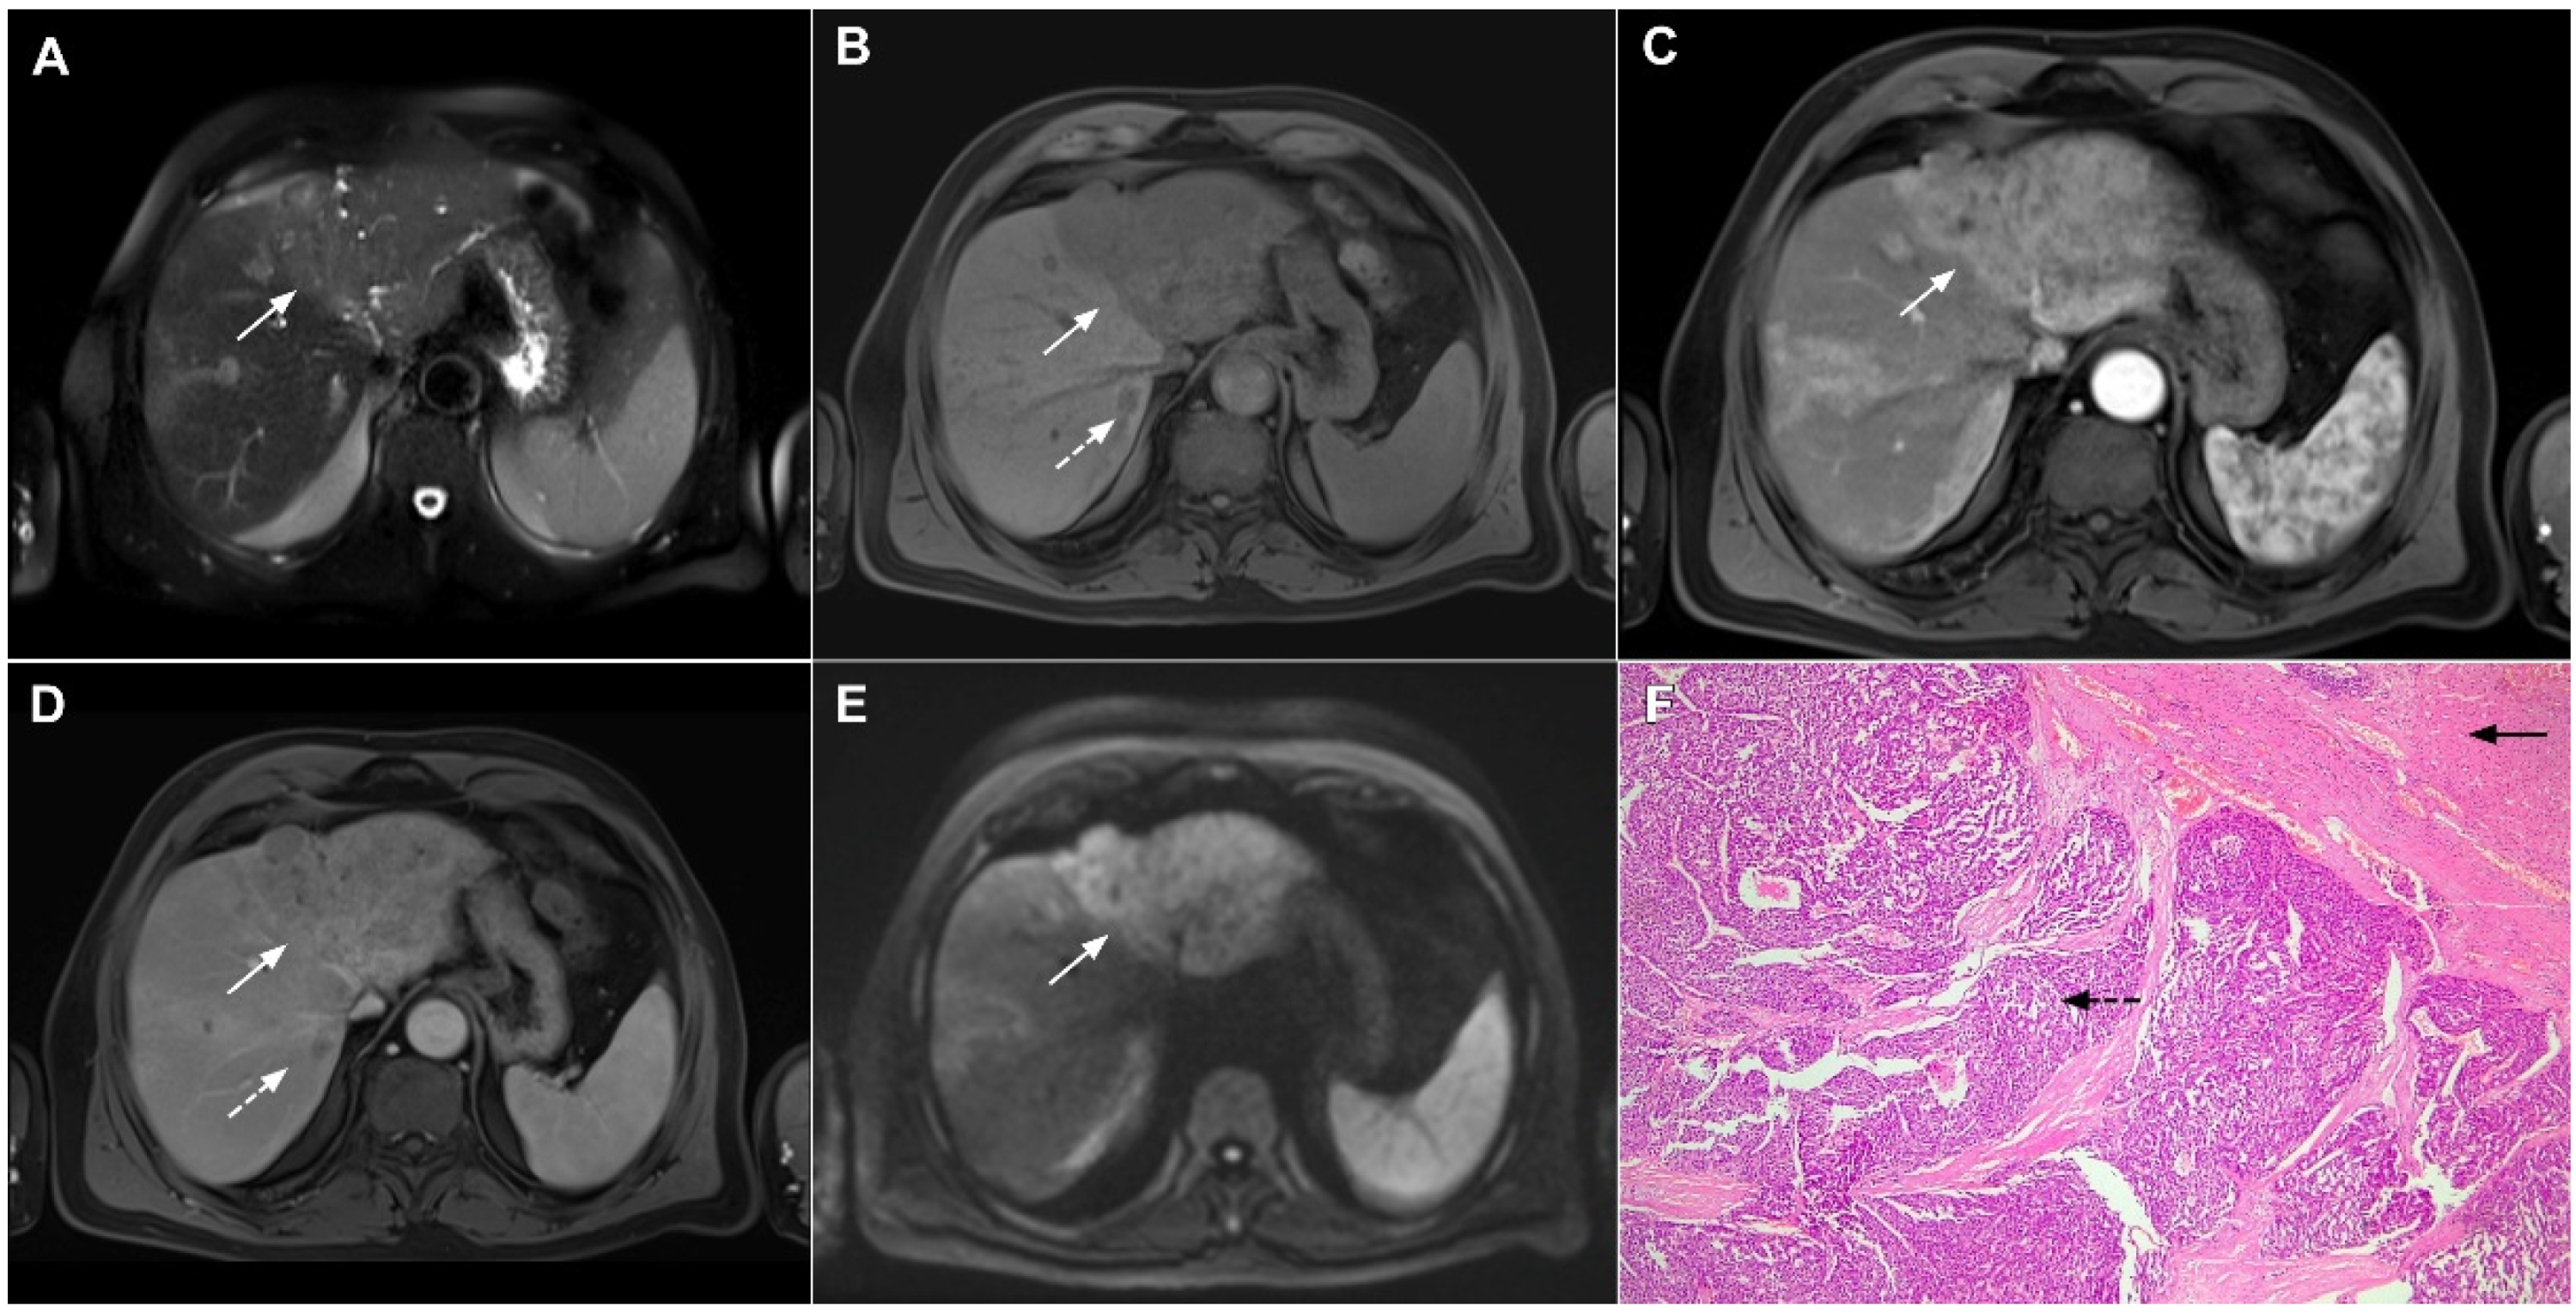

Figure 6.

Hypervascular mass-forming cholangiocarcinoma in a 63-year-old woman. The axial T2-weighted image (A) shows a moderately hyperintense tumor (arrow) located in liver segments VI and VII with a subtle medial capsular retraction. The lesion (arrow) is hypointense on the plain T1-weighted image (B), hypervascular in the arterial phase (C) with washout on the portal venous phase (D). The tumor (arrow) is hyperintense on DWI (E). Hematoxylin and eosin (H&E) staining (F) showed well-differentiated cholangiocarcinoma (arrow) surrounded by normal liver parenchyma (dashed arrow); original magnification ×40.